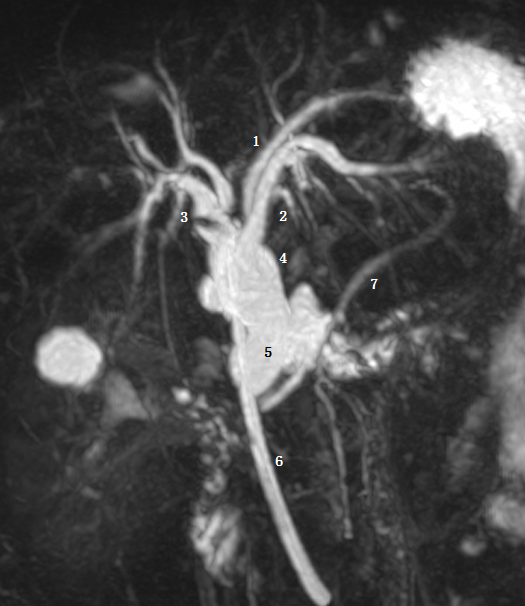

图为胆总管结石继发梗阻患者。Ⅱ型:肝右前、右后肝管与肝左管汇合肝总管,呈三叉状,1 为肝右前肝管,2 为右后肝管,3 为肝左管,4 为肝总管,箭头为肝总管及胆总管结石。 医学百科网 | YxBaike.Com

Ⅲb 型为右后肝管汇入肝总管。图 1 为右前肝管,2 为肝左管,3 为右后肝管,4 肝总管,5 胆囊管,6 胆总管。 医学百科网 | YxBaike.Com

Ⅴ型为副肝管的存在。图示 1 为肝右管,2 为肝左管,3 为副肝管,4 为肝总管,5 为胆囊管,6 为胆总管。 医学百科网 | YxBaike.Com

Ⅵ型为 2、3 段分级肝管汇入右肝管或肝总管。图为胆总管末端梗阻 T 管引流术后。图示 1 为 2 段肝管,2 为 3 段肝管,3 为肝右肝管,4 为肝总管,5 为胆总管,6 为 T 型管,7 胰管。 医学百科网 | YxBaike.Com